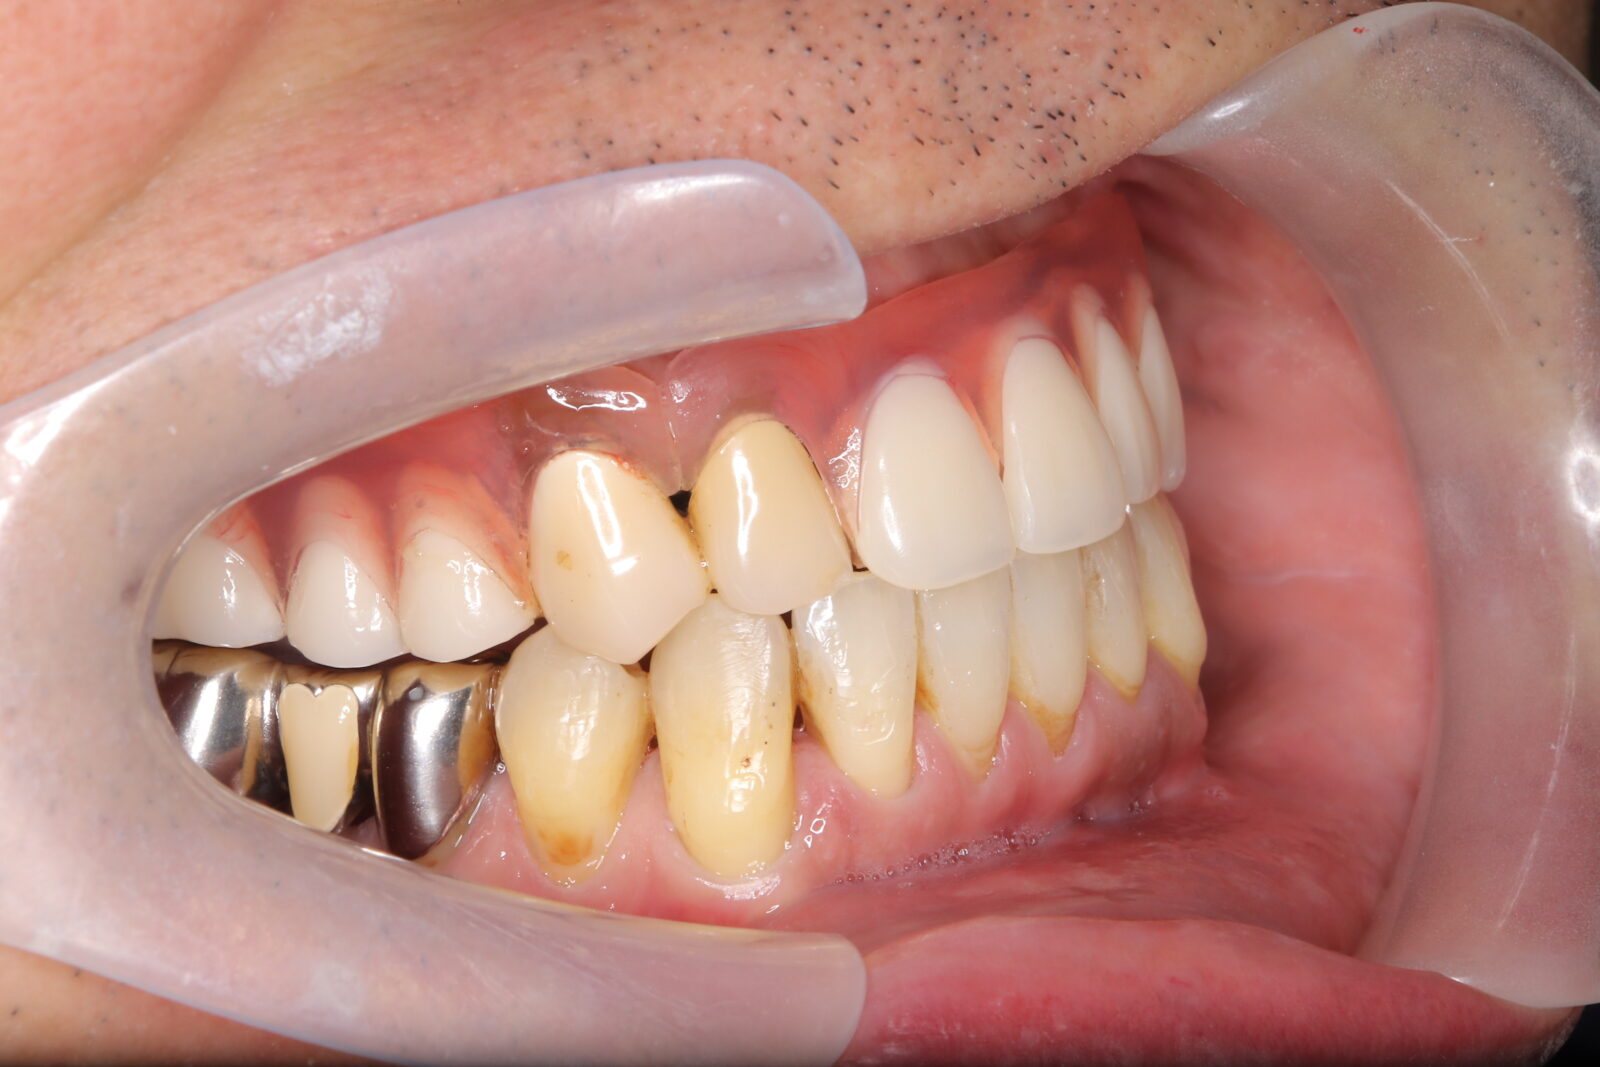

矯正と補綴が必要で実施した症例

左側に隙間。歯の数が少ない。もともと2番と7番がない。(先天欠如)歯の数が少ないため上顎のアーチ全体が小さい。歯槽骨の幅も狭く、歯肉も薄い。骨質も弱かった。

上顎左右2番と6番が先天欠如。下顎左右1番も先天欠如でもともとブリッジが装着されていた。

左右非対称なすきっ歯。上顎の前歯がないので左側の隙間を左右2番相当部に集めた。

上下の前歯が反対の噛み合わせ(受け口)で、干渉しているためうまく閉じることができず、奥歯は左右同時に噛めないので、どこかにずらさないと口を閉じられない。

左右の歯を同時に合わせることができず、どこで噛んだら良いかわからない噛み合わせでした。

小臼歯部は噛み合うことがない側方の開口状態。矯正と補綴が必要なケース。 主訴は顎の不調と歯軋り、夜間の食いしばり。

マルチブラケットとインビザラインを併用し、クラウンとブリッジを装着しました。

上顎左右2番は、歯が入るスペースを作り、ブリッジを装着しました。

他の歯医者で何軒も断られていました。 骨の幅がうすくインプラントはできない。骨の質も柔らかい。PCR検査の結果も歯周病ハイリスク患者でした。

歯の位置は、本人の顎が安定する場所を探して着地した。 左右で噛み合わせが非対称で、理想的な歯のポジションを獲得できなかったものの、左右同時に噛むことができるようになった。

顎関節の症状も落ち着いて、開口障害や、顎の痛みは無くなった。

矯正治療はどの装置を選択しても歯周病のリスクを高めてしまう。

これ以上の歯の移動が歯周病と骨質、骨の代謝のバランスの兼ね合いで困難であると判断し、ここが着地点とした。